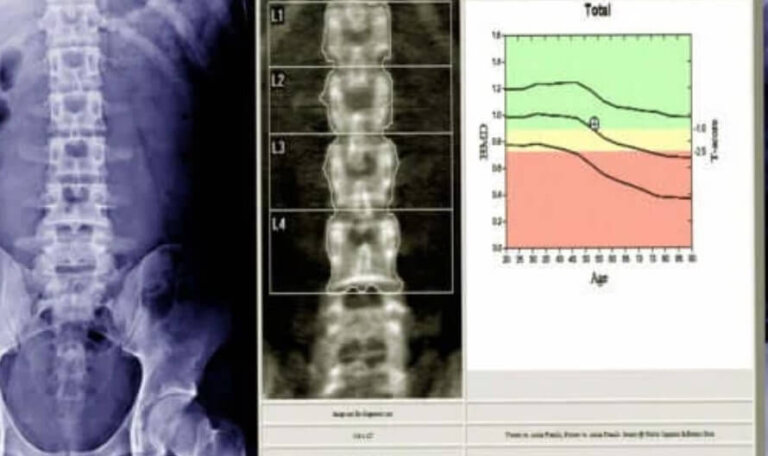

Η πυκνομετρία των οστών (γνωστή με το ακρωνύμιο DEXA ή DXA) είναι μια εξέταση για τον προσδιορισμό της οστικής πυκνότητας. Βοηθά να προσδιοριστεί εάν υπήρξε απώλεια ακεραιότητας ή ανοργανοποίησης στον οστικό ιστό.

Σύμφωνα με ένα άρθρο στο RadiologyInfo.org, χρησιμοποιεί μια μικρή δόση ιονίζουσας ακτινοβολίας. Ως αποτέλεσμα, καθιστά δυνατή τη λήψη εικόνων από τα οστά. Το τεστ είναι γρήγορο, απλό και μη επεμβατικό.

Επικεντρώνεται συνήθως στα οστά του ισχίου, της σπονδυλικής στήλης και του αντιβράχιου. Ωστόσο, μπορούν επίσης να εξετάσουν άλλα μέρη όπως η φτέρνα, τα δάχτυλα ή ο καρπός.

Οι γιατροί συνήθως ερμηνεύουν τα αποτελέσματα της πυκνομετρίας των οστών. Η Sociedad Española de Geriatría Gerontología περιγράφει ότι λαμβάνετε μια σειρά ψηφιοποιημένων και έγχρωμων εικόνων. Πρέπει να τις συγκρίνουν με τις τιμές που ορίζονται ως φυσιολογικές για την ηλικιακή ομάδα και το φύλο στο οποίο ανήκει ο ασθενής.

Με αυτόν τον τρόπο, αποκτούν δύο τιμές ή βαθμολογίες.

- Η πρώτη είναι η βαθμολογία Τ, η οποία αναφέρει την ποσότητα της οστικής πυκνότητας σε σύγκριση με έναν ενήλικα του ίδιου φύλου που έχει τη μέγιστη οστική ικανότητα. Η βαθμολογία Τ κάτω από -1.1 είναι χαμηλή, δηλαδή οστεοπενία. Η βαθμολογία Τ πρέπει να είναι κάτω από -2,5 για να υπάρχει οστεοπόρωση.

- Η άλλη βαθμολογία που μπορούν να λάβουν είναι το Ζ. Αυτό συγκρίνει τον ασθενή με μια ομάδα ατόμων της ίδιας ηλικίας, φύλου και παρόμοιας φυσικής κατάστασης. Τους επιτρέπει να παρακολουθούν την πορεία της θεραπείας.